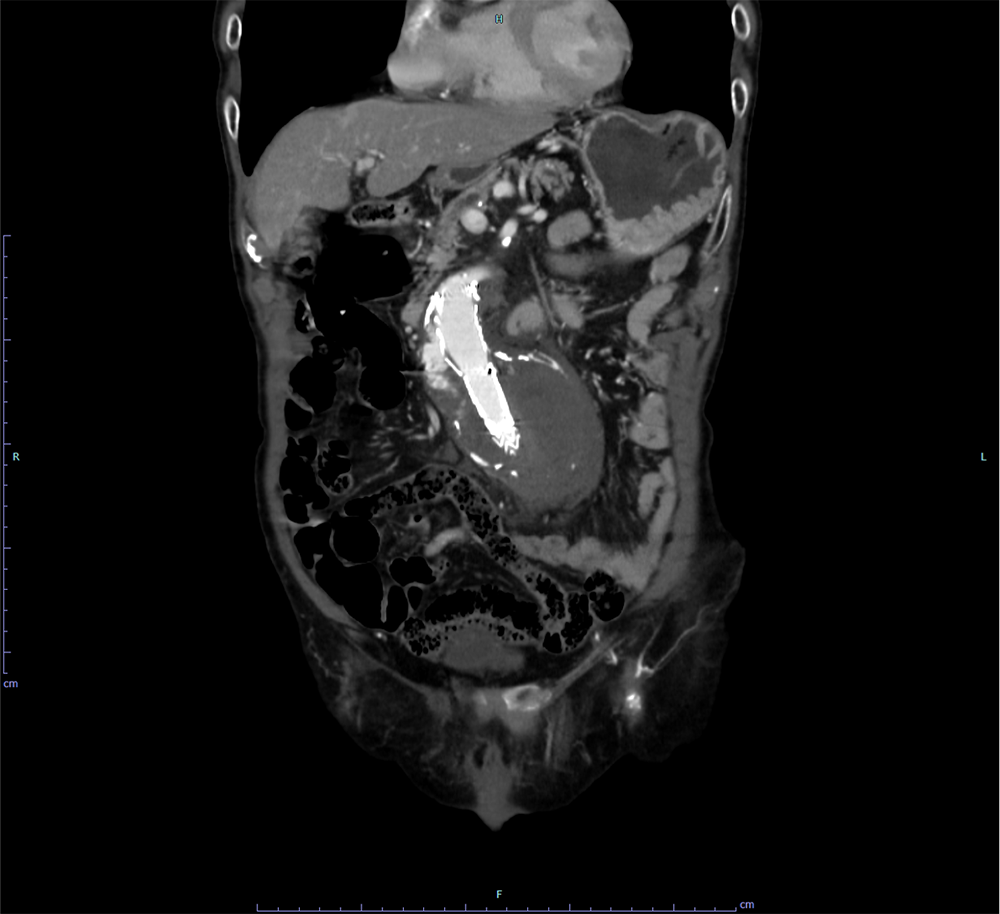

EVAR後の腹部大動脈瘤破裂に対し追加EVARを施行した一例

当科で腹部大動脈瘤に対しEVAR術後、瘤増大傾向で外来フォローアップされていた。急激な腹痛で来院し造影CTが撮影された。瘤内にType1aエンドリークを認めるほか、瘤内解離、破裂を認めた。緊急で追加EVARが行われ、治療後エンドリークは消失し、術後経過も問題なく退院となった。

腹部大動脈瘤(AAA)の診断と治療戦略の決定において、造影CTは最も信頼性の高い検査である。造影CTにより瘤の存在部位や最大径、長さ、形状を正確に評価でき、拡大速度や形態の異常といった破裂リスクの判定にも用いられる。また、瘤壁の不整、壁在血栓、壁内血腫の有無を描出することで、切迫破裂や破裂の診断に直結する。さらに、腎動脈・内腸骨動脈・下腸間膜動脈など主要分枝との位置関係を明らかにすることで、開腹術かEVARかといった治療適応の判断やステントグラフトのデザイン決定に不可欠である。未破裂AAAの経過観察にもCTが推奨されており、腹部超音波に比べ測定誤差が少ない一方、腎機能障害などの可能性を考慮する必要がある。破裂または切迫破裂が疑われる場合には、後腹膜血腫や造影剤漏出を迅速に描出し、緊急治療の判断に直結するため、診断と治療計画の双方において中心的役割を担う。